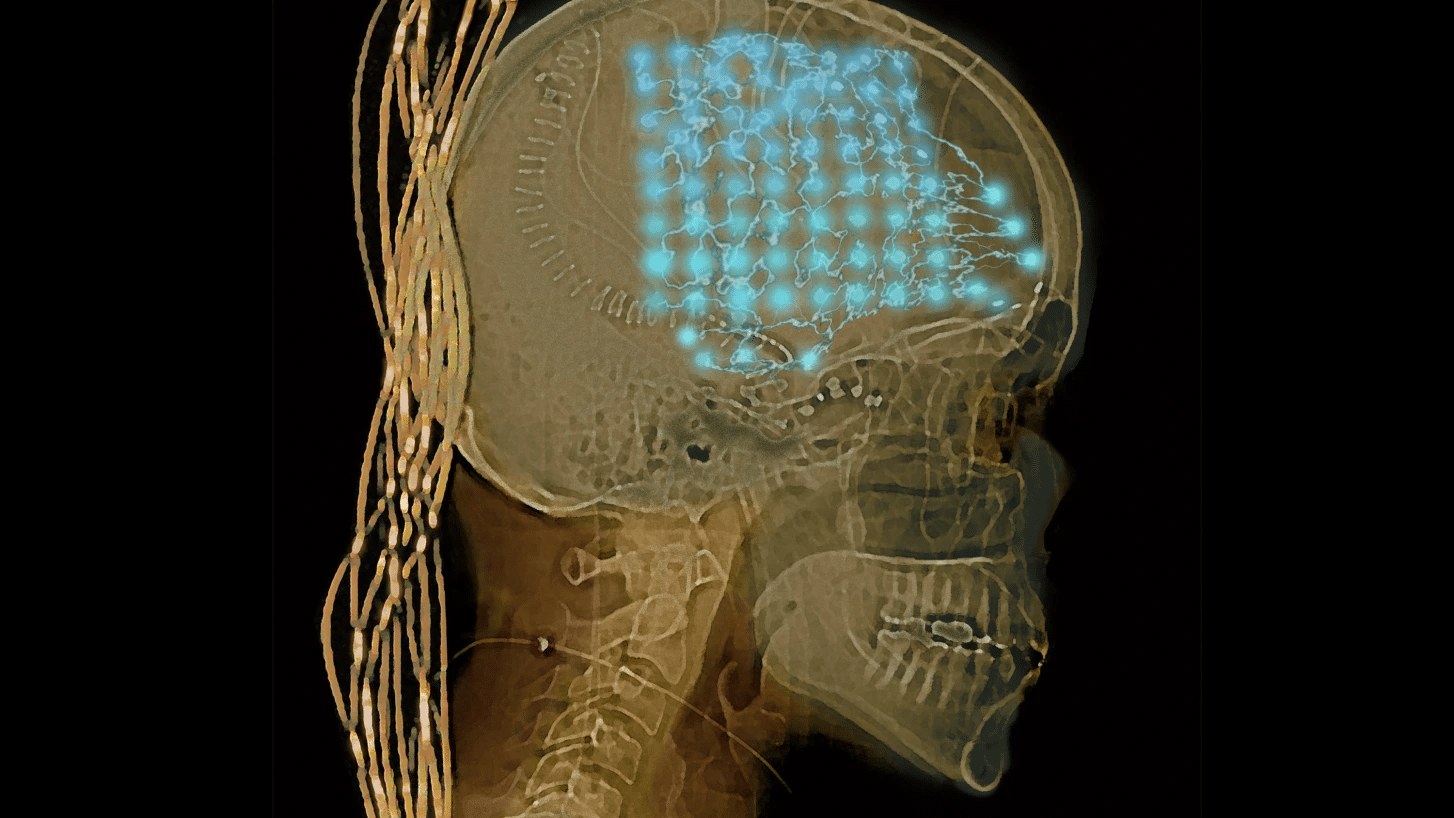

STYLIZED CT: MICHAEL WARD

Neuroscientists listened in on people’s brains for a week. They found order and chaos.

일상 생활 속 인간의 뇌 상태를 관찰하다

신경과학자들이 일주일에 걸쳐 뇌 활성을 추적 관찰한 결과, 평상시 인간 두뇌는 안정과 혼돈 사이에 존재하는 것으로 나타났다. 이 발견은 추후 뇌신경 질환 치료에 도움을 줄 수 있다.

일상생활 속 인간의 두뇌가 안정과 혼돈 상태의 중간에 존재한다는 연구 결과가 나왔다. 연구진은 참여자들의 두뇌 활성을 일주일 동안 기록하여 이 사실을 밝혀냈다. 예를 들어 책을 읽다가 친구와 이야기를 나눌 때 사람의 뇌는 준안정(semi-stable) 상태에서 또 다른 준안정 상태로 전환된다. 이 과정에서 뇌는 완전한 무작위적인 패턴으로 다른 여러 가지 상태를 무질서하게 경유하는 것으로 나타났다.

혼돈 상태에 있던 뇌가 어떤 방식으로 안정을 회복하는지 밝혀지면, 극도의 안정이나 불안정으로 인해 나타나는 양극단의 질환을 치료하는 데 도움을 줄 수 있을 것이다. 연구에 참여한 신경과학자들은 뇌의 지나친 혼돈이 발작을 일으킬 가능성이 있는 반면, 지나친 안정은 사람을 혼수상태에 빠뜨릴 수 있다고 말한다.

뇌에서 어떤 일이 일어나는지 깊이 이해하면 언젠가 뇌 자극을 이용해 뇌를 두 극단 사이 최적의 지점으로 유도할 수 있을 것이다.